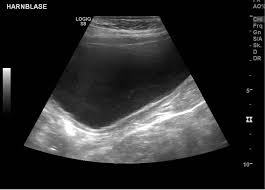

Die Ultraschalluntersuchung Sonografie ist meist die erste bildgebende Untersuchung bei Verdacht auf Blasenkrebs. Die Klassifikation Stadieneinteilung oder Staging genannt ist ein wichtiger Baustein für die Wahl der optimalen Therapie. Dabei kann der Arzt Blase Nieren und Harnwege begutachten.

Eine Ultraschalluntersuchung ermöglicht auch Blasensteine oder einen Blasentumor zu entdecken. Wirken Lymphknoten verdächtig veranlassen Ärzte in der Regel eine Biopsie oder Lymphknotenentnahme. Per Ultraschall lassen sich auch mögliche andere Ursachen für Beschwerden erkennen beispielsweise Nieren- Blasen-. Blasenkrebs kann als Folge einer Strahlentherapie entstehen. Blasenkrebs Mit der Diagnose Blasenkrebs hat der Patient nicht gerechnet. Sofern der Verdacht auf Blasenkrebs besteht nimmt der Arzt eine gründliche Untersuchung vor. Sie stellt zusammen mit der Biopsie Gewebeprobeentnahme die wichtigste Untersuchung für die Diagnose von Blasenkrebs dar. Ziel der Diagnostik ist eine möglichst frühzeitige Diagnosestellung und die Erhärtung oder Ausräumung des Verdachts auf Blasenkrebs. So stellen Ärzte beispielsweise bei Patienten mit einem Gebärmuttertumor ein erhöhtes Risiko für.

Die wichtigste Untersuchung zur Diagnose-Stellung ist die Spiegelung der Harnblase die sogenannte Zystoskopie. Es gibt keine Tumormarker im Blut die spezifisch für Blasenkrebs sind. Per Tastuntersuchung nimmt er dabei die Nierengegend den Unterbauch und die Geschlechtsorgane unter die Lupe. Blasenkrebs Mit der Diagnose Blasenkrebs hat der Patient nicht gerechnet. Liegt ein invasiver Harnblasentumor vor sind tiefgreifende Maßnahmen nötig. Wirken Lymphknoten verdächtig veranlassen Ärzte in der Regel eine Biopsie oder Lymphknotenentnahme. Die Ultraschalluntersuchung Sonografie ist meist die erste bildgebende Untersuchung bei Verdacht auf Blasenkrebs.